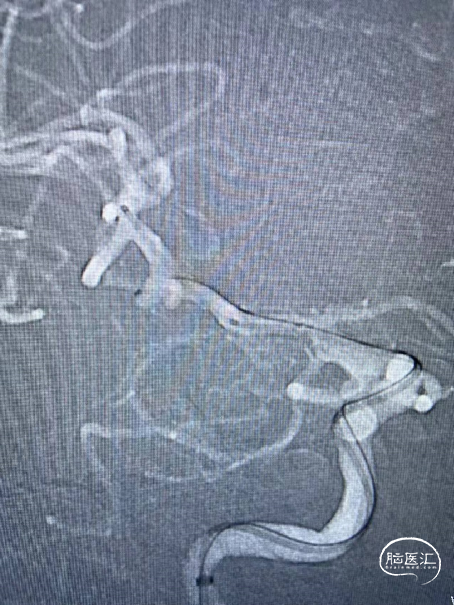

Synchro-0.014 200mm微导丝携带下将PROWLER SELECT PLUS微导管送至左侧大脑中动脉M2段,在ASAHI CHIKAI-0.014 200cm微导丝携带下将Echelon 10微导管送至左侧颈内动脉交通段动脉瘤内,将4mm×12cm 3D弹簧圈(EV3)沿微导管置入动脉瘤腔内,沿支架微导管将4.5mmx22mm支架(Enterprise)置入左侧颈内动脉交通段,沿Echelon10微导管分别将4mm×8cm2D(泰杰伟业),3mm×8cm 3D(EV3),2.5mm×6cm 3D(EV3),1.5mm×2cm 2D(泰杰伟业),1.5mm×2cm 2D(泰杰伟业)弹簧圈沿微导管置入动脉瘤腔内,复查造影示动脉瘤栓塞致密,载瘤动脉通畅,复查颅内正侧位造影右侧颈内动脉、大脑前动脉、大脑中动脉显影良好。

路图引导下将4mm×12cm 3D弹簧圈(EV3)沿微导管置入动脉瘤腔内暂不解脱,沿支架微导管将4.5mmx22mm支架(Enterprise)置入左侧颈内动脉交通段。继续填入弹簧圈

术后正侧位所见